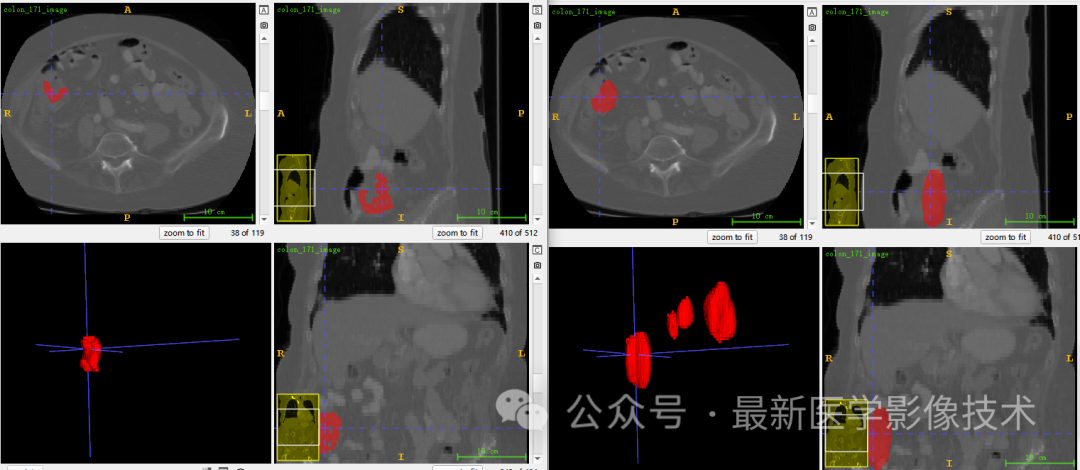

5、验证集分割结果

左图是金标准结果,右图是预测结果。